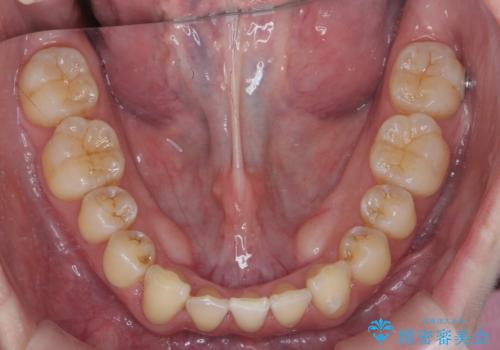

短期間できれいな歯並びになり、大変満足していただきました。

- 1年

- インビザライン